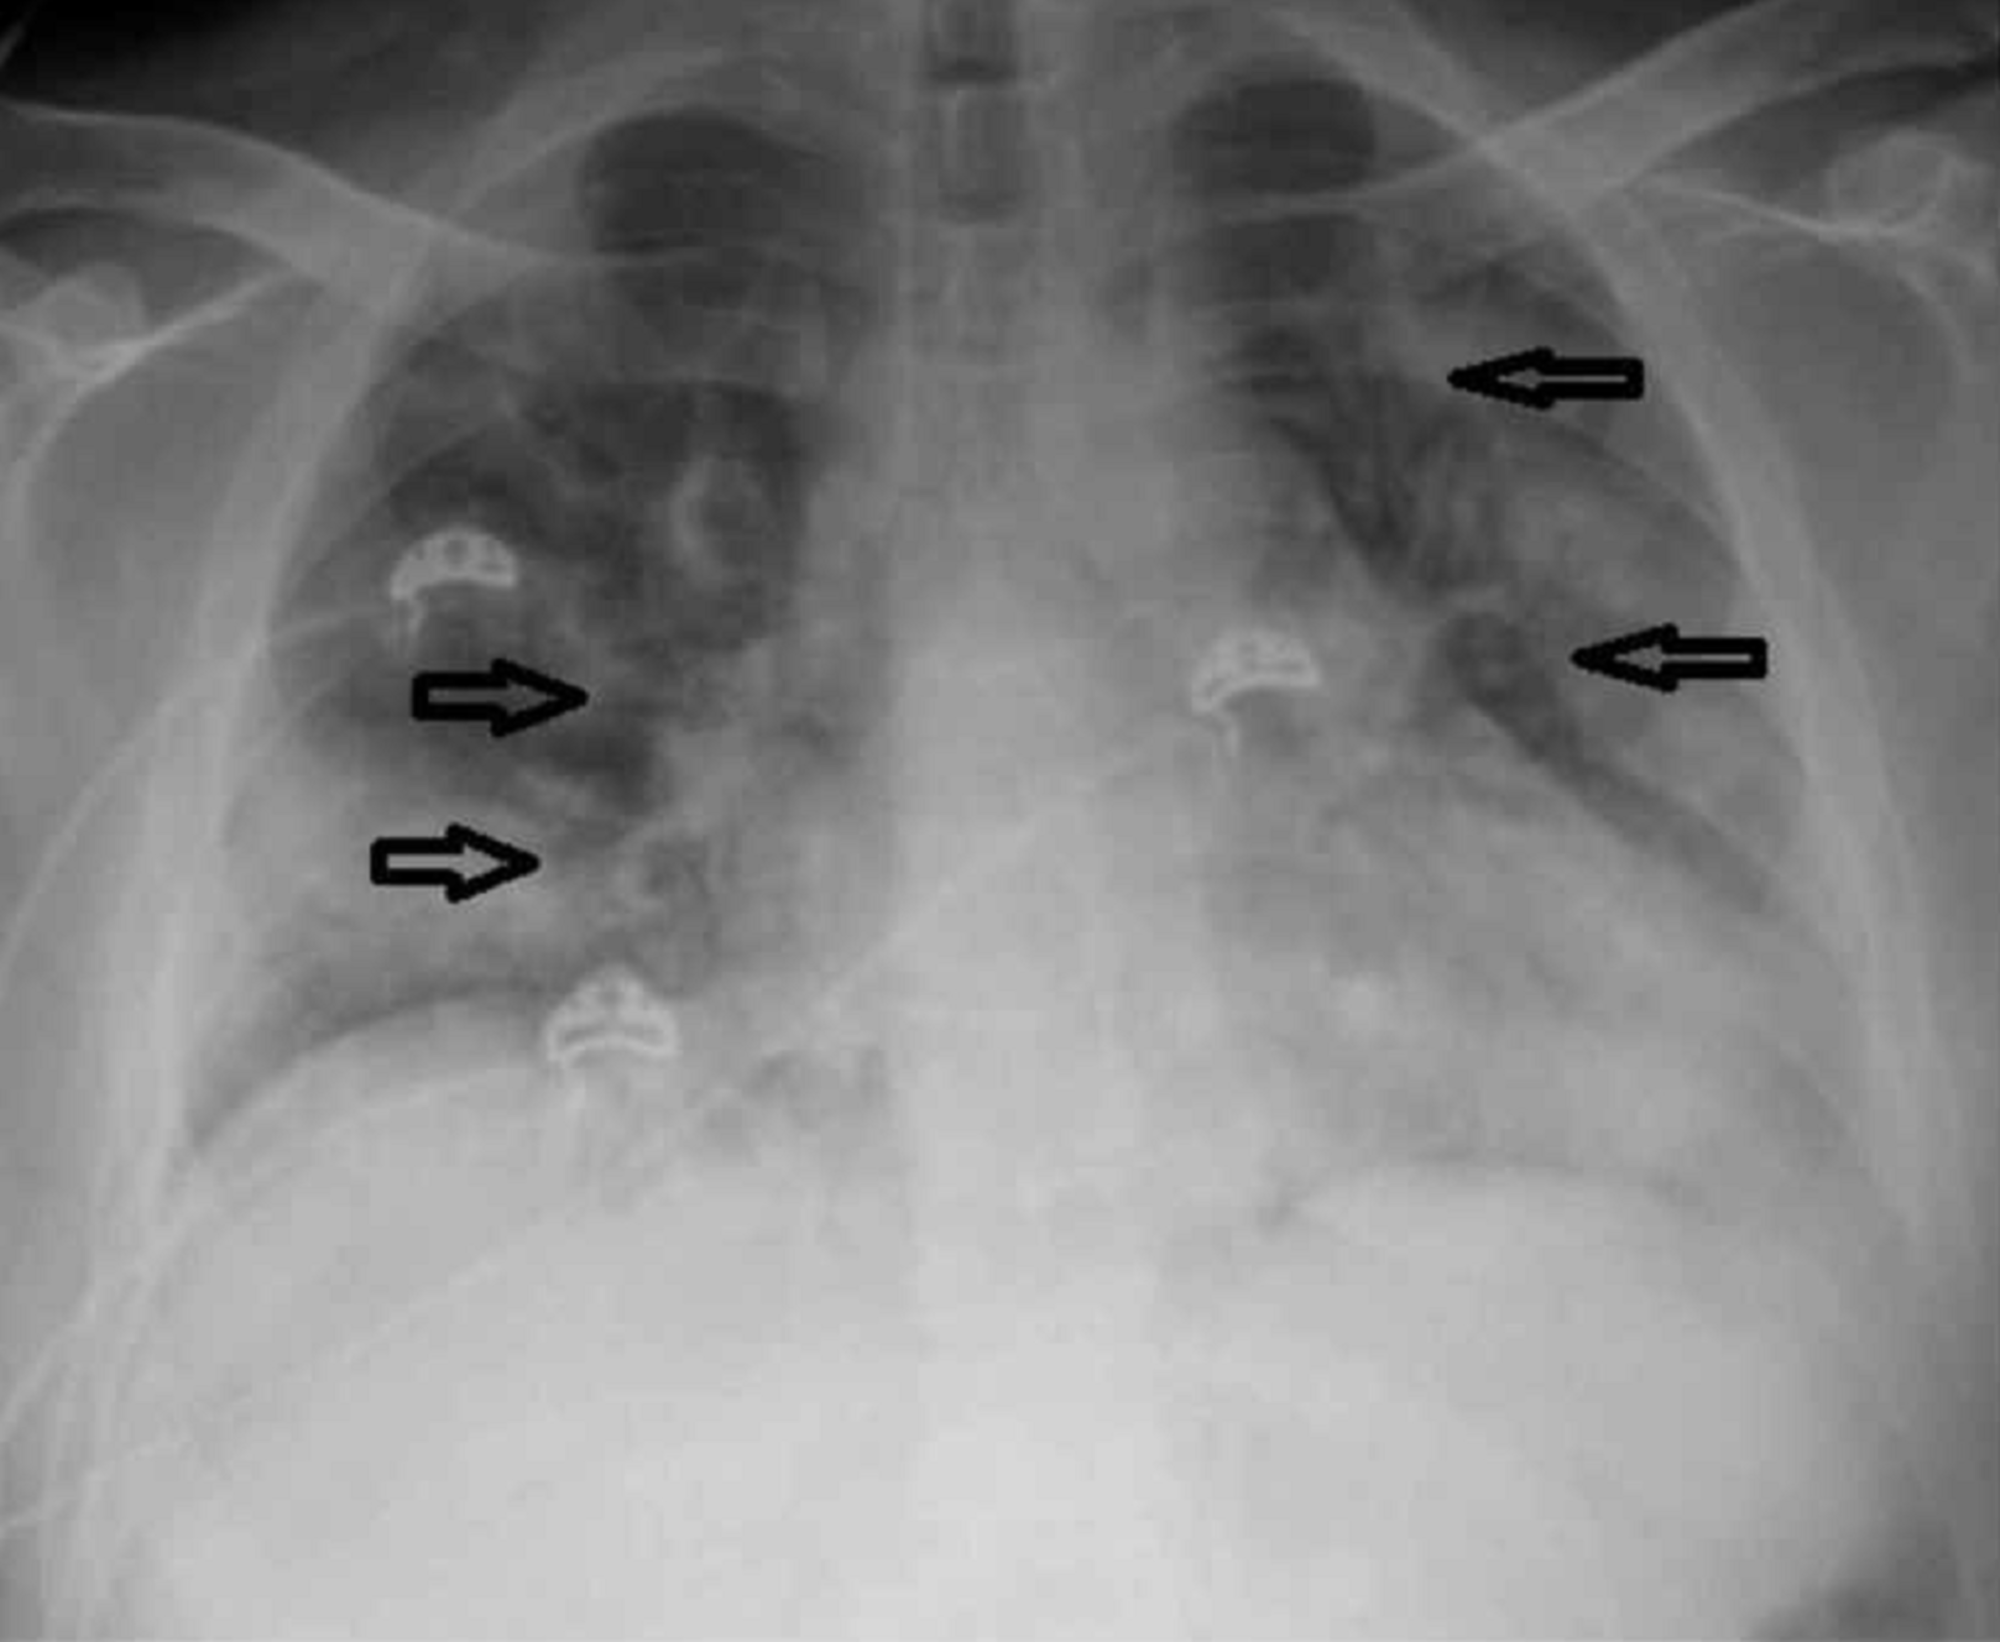

The chest X-ray revealed cardiomegaly with bilateral lung infiltrates (Figure 1). Computed tomography (CT) of the chest without contrast revealed prominent multifocal pneumonia and multiple ground-glass airspace opacities throughout all lung fields (Figure 2).